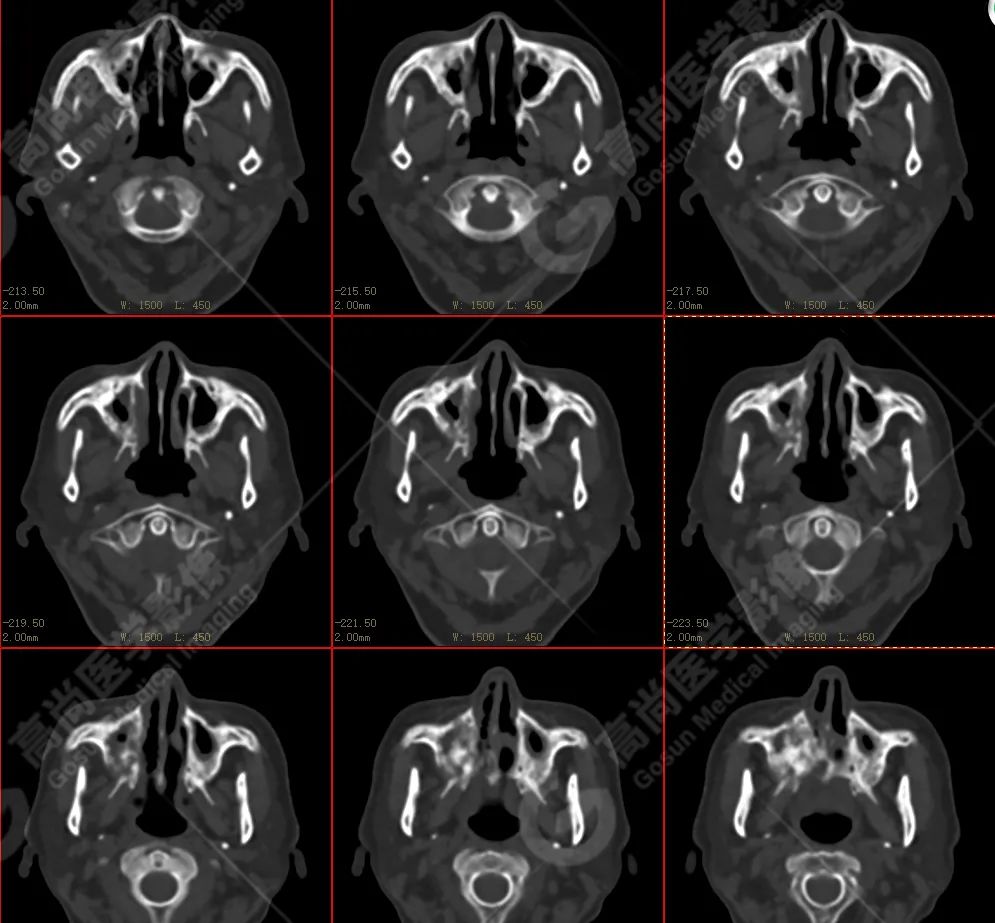

右侧上颌骨-上颌窦骨壁-骨性鼻中隔区域见片块状放射性摄取异常增高影,最大层面约 4.1 cm×3.8 cm×2.8 cm,SUV 最大值为 10.4,CT 示上述部位见成骨性改变,骨质不均匀弥漫性增厚、密度不均匀增高,并可见肿瘤骨影,边缘毛糙,周围伴软组织增厚。